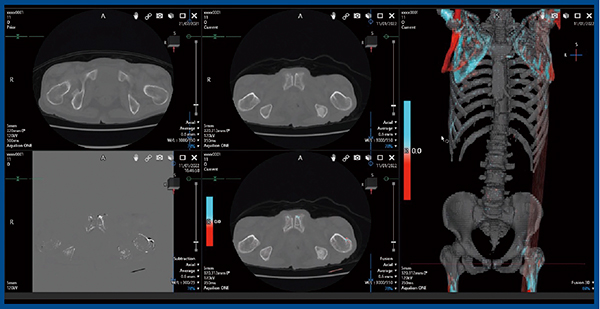

症例1は,60歳代,男性の前立腺がんで,ホルモン療法休薬中である。多発骨転移があり,3Dフュージョン画像では,椎体に骨病変が多発していることがわかる(図2)。本症例は右大腿骨にも転移があり,硬化性変化が認められた。

図2 症例1:60歳代,男性,前立腺がん